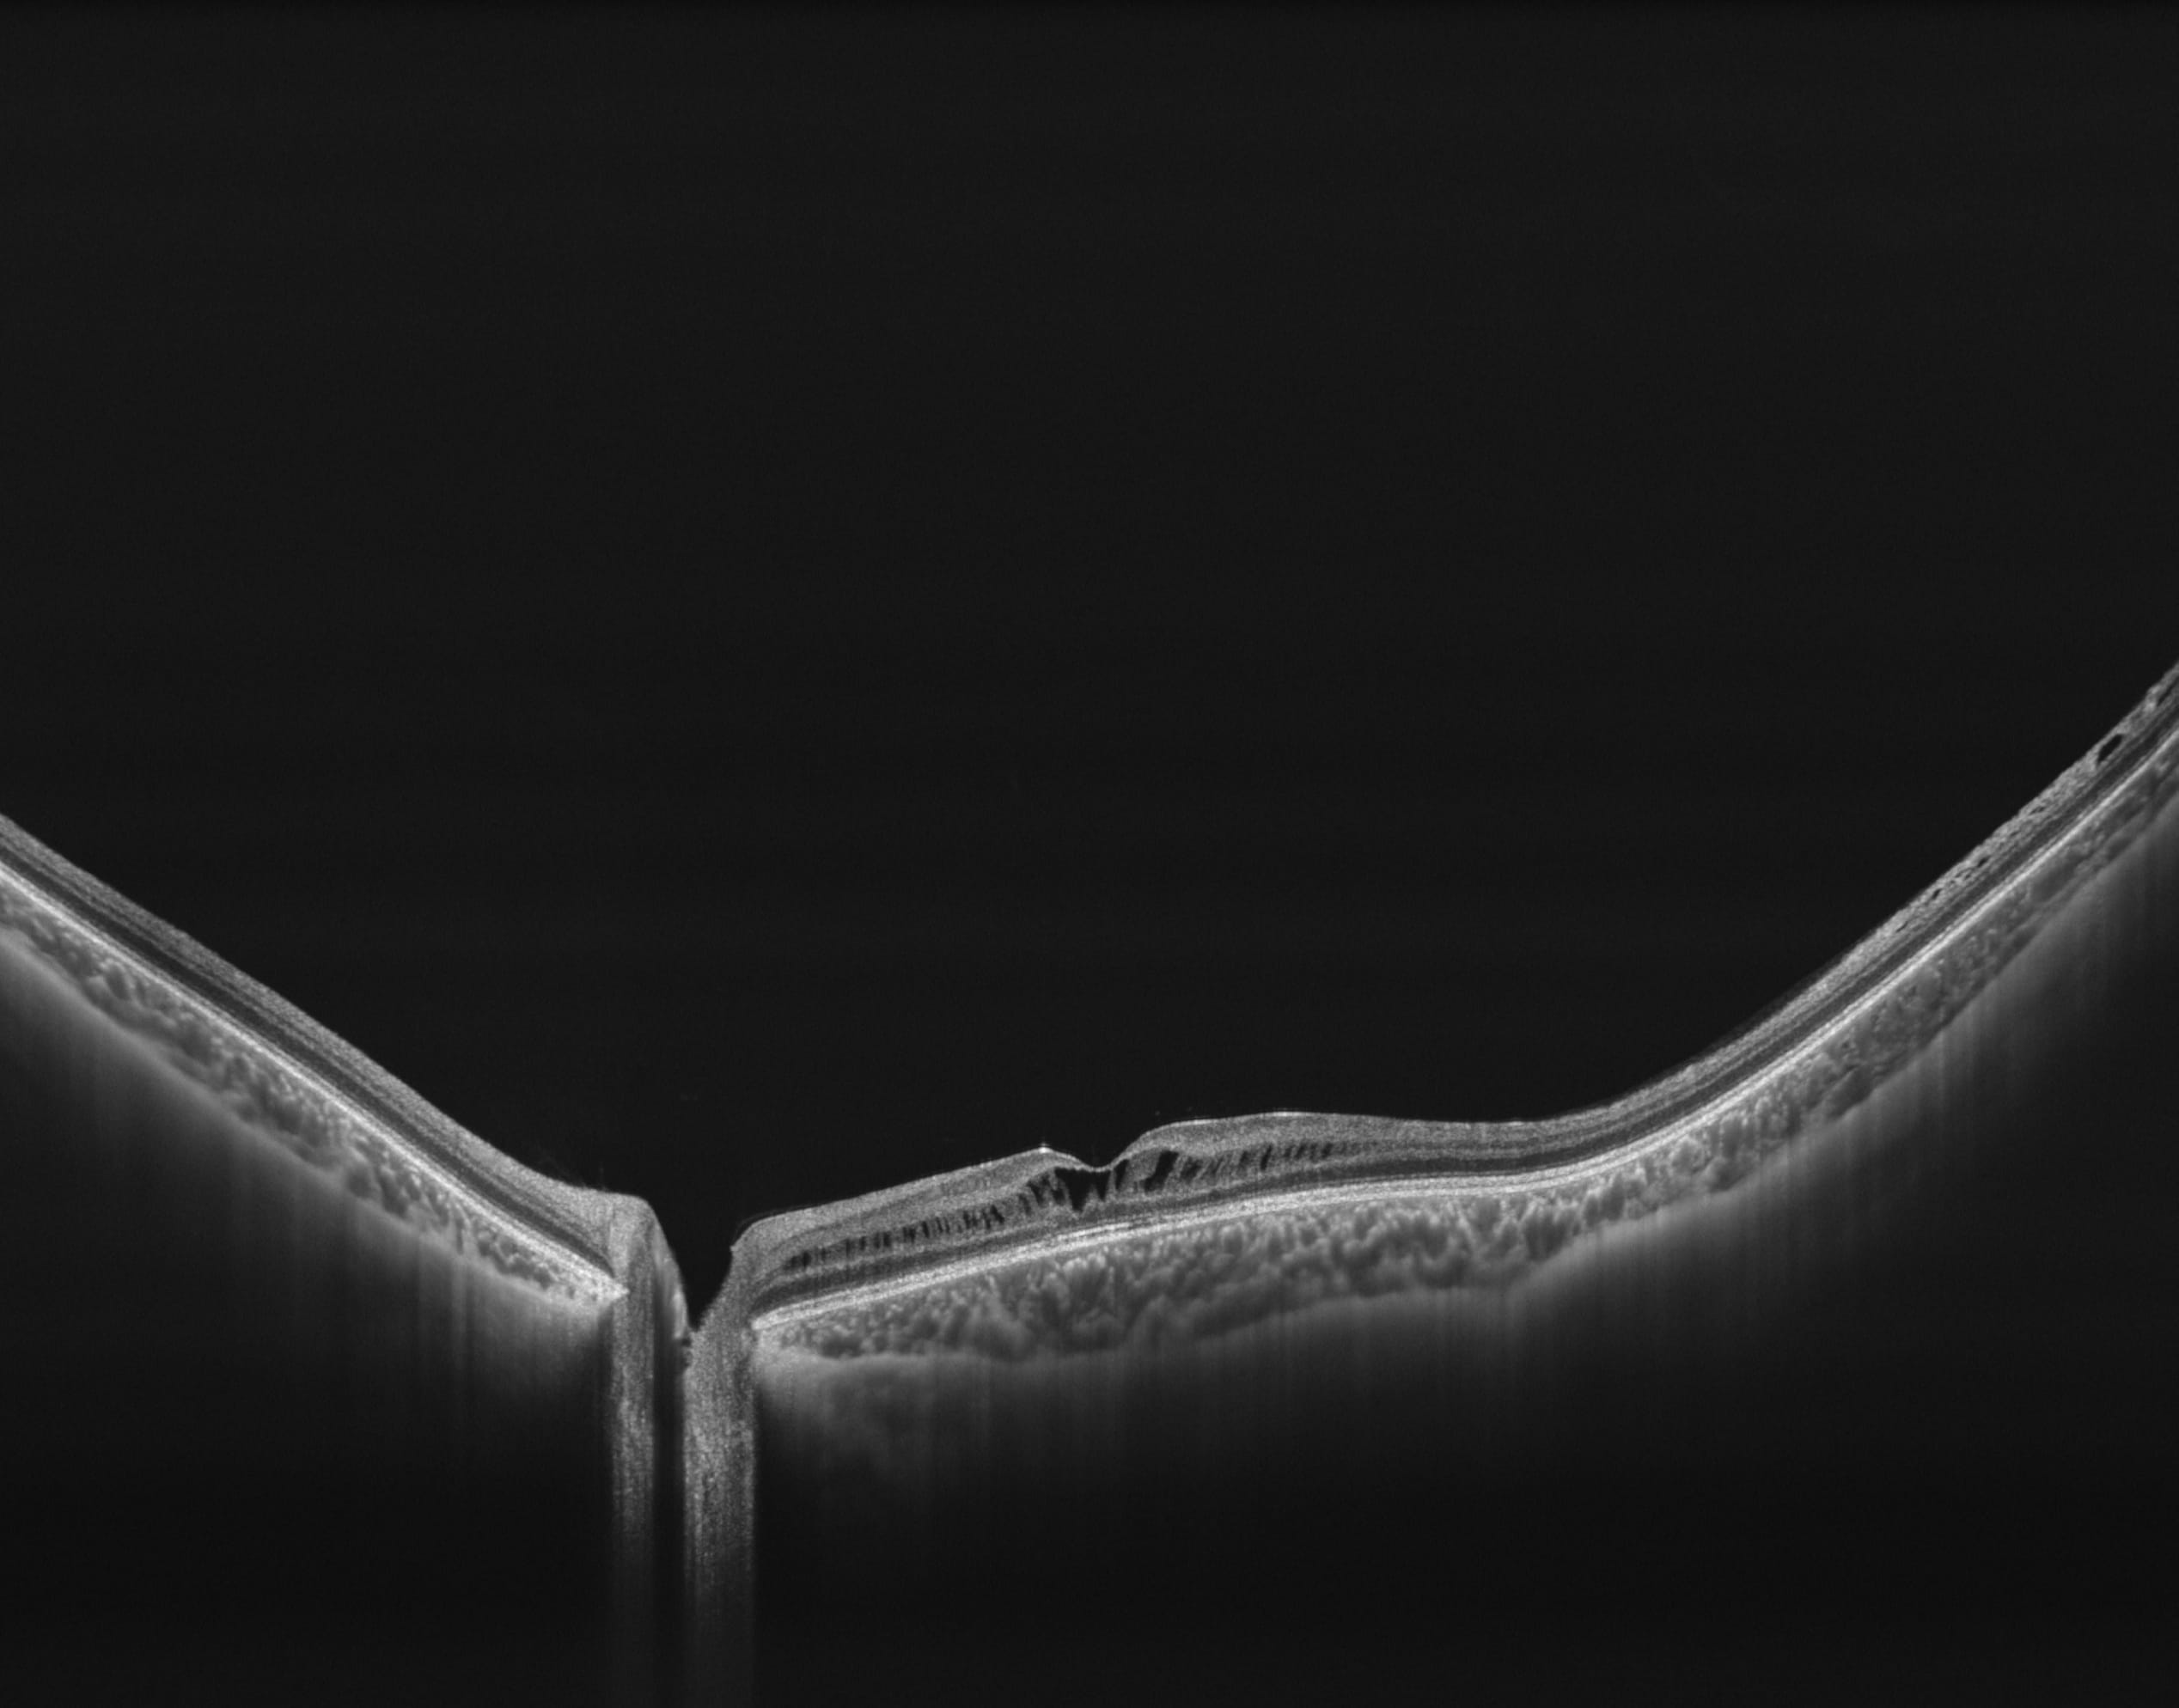

400kHz speed full-range swept-source OCT for anterior and posterior

- Full-Range wide-field Swept Source OCT

- Choroid OCTA with Quantification Parameters